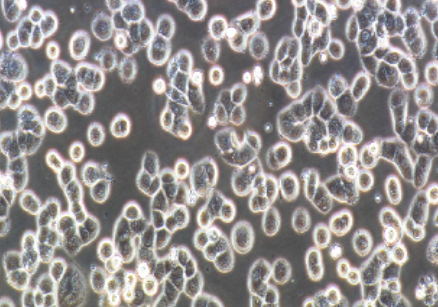

MDA-MB-468细胞是由Cailleau·R等人于1977年从一位患有转移性乳腺癌的51岁黑人女性的胸腔积液中分离得到的。虽然供体组织的G6PD等位基因杂合,但MDA-MB-468细胞始终表现为G6PD A表型。p53MDA-MB-468细胞是由Cailleau·R等人于1977年从一位患有转移性乳腺癌的51岁黑人女性的胸腔积液中分离得到的。虽然供体组织的G6PD等位基因杂合,但MDA-MB-468细胞始终表现为G6PD A表型。p53基因273位密码子存在GA突变,从而导致ArgHis替代。每个MDA-MB-468细胞上存在1×10^6EGF受体。

上皮细胞样,贴壁生长